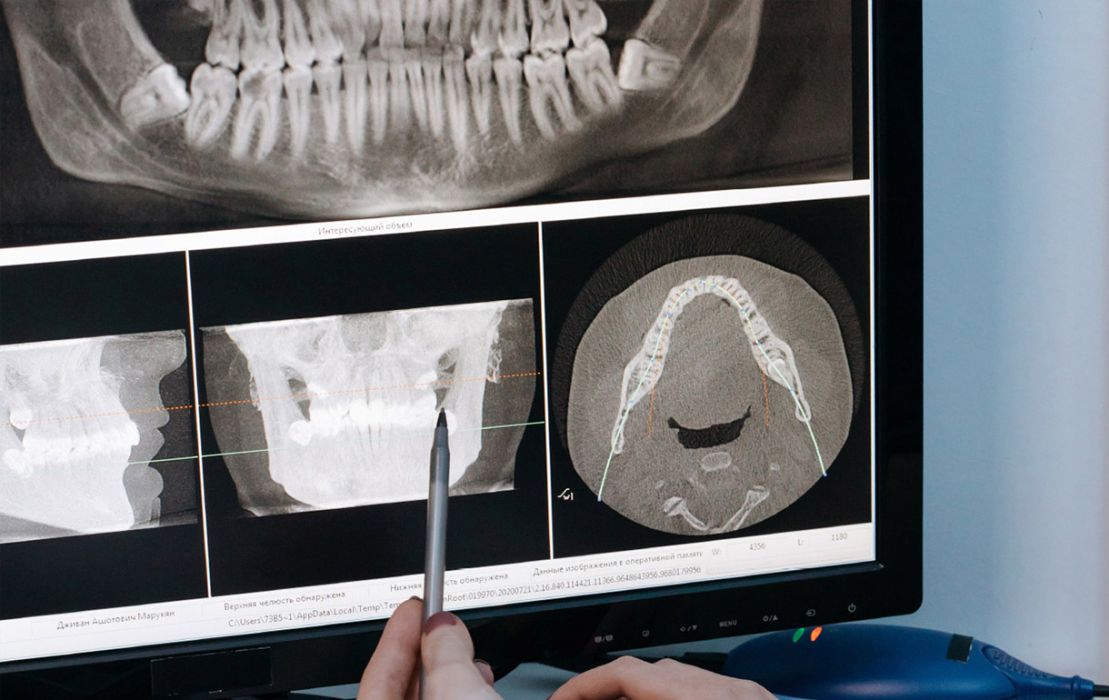

Radiologia Digitale

L'utilizzo della rx panoramica digitale e del cone beam consentono di indagare scrupolosamente lo stato di salute del cavo orale con il minor carico di radiazioni possibile.